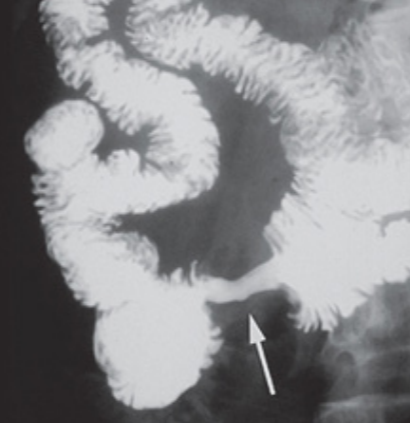

- Obstrutivos: Dor em cólica e vômitos (comuns em lesões duodenais proximais). A imagem radiológica pode mostrar o sinal da “maçã mordida”.

caso de tumor neuroendócrino metastático de intestino delgado com quadro característico de síndrome carcinoide. Fonte: https://doi.org/10.1590/0102-672020190001e1492